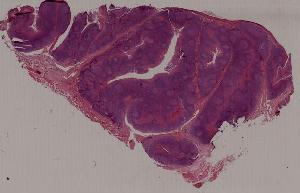

1.心肌褐色萎缩心肌肥大

2.肾曲管上皮混浊肿胀

3.肝细胞脂肪变性

4.脾包膜玻璃样变

5.血管壁纤维样坏死

6.肝细胞凝固性坏死

7.脑液化性坏死

10.肝淤血

11.淤血性肝纤维化

12.急性肺淤血

13.慢性肺淤血

14.混合血栓

15.机化血栓

16.肾贫血性梗死

17.肺出血性梗死

18.假膜性肠炎

19.蜂窝织性阑尾炎

20.肺脓肿

21.慢性扁桃体炎

22.慢性宫颈炎

第一页